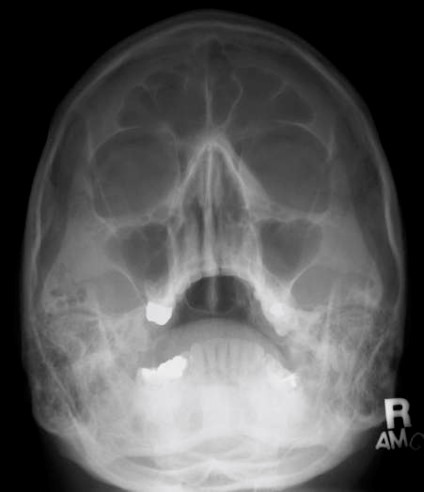

- PNS(paranasal sinus, 부비동(접형동, 상악동, 전두동, 사골동) 관찰

- 골절, 및 염증 평가.

Water's view

- 턱을 올려 MML(mento-meatal line) 턱끝과 외이도를 잇는 선이 카세트와 90도를 이루게 한다.

- 이러면 자연히 OML(Orbito meatal line)과 카세트가 37도를 이룬다

- petrous ridge가 상악동 아래에 보여야 한다